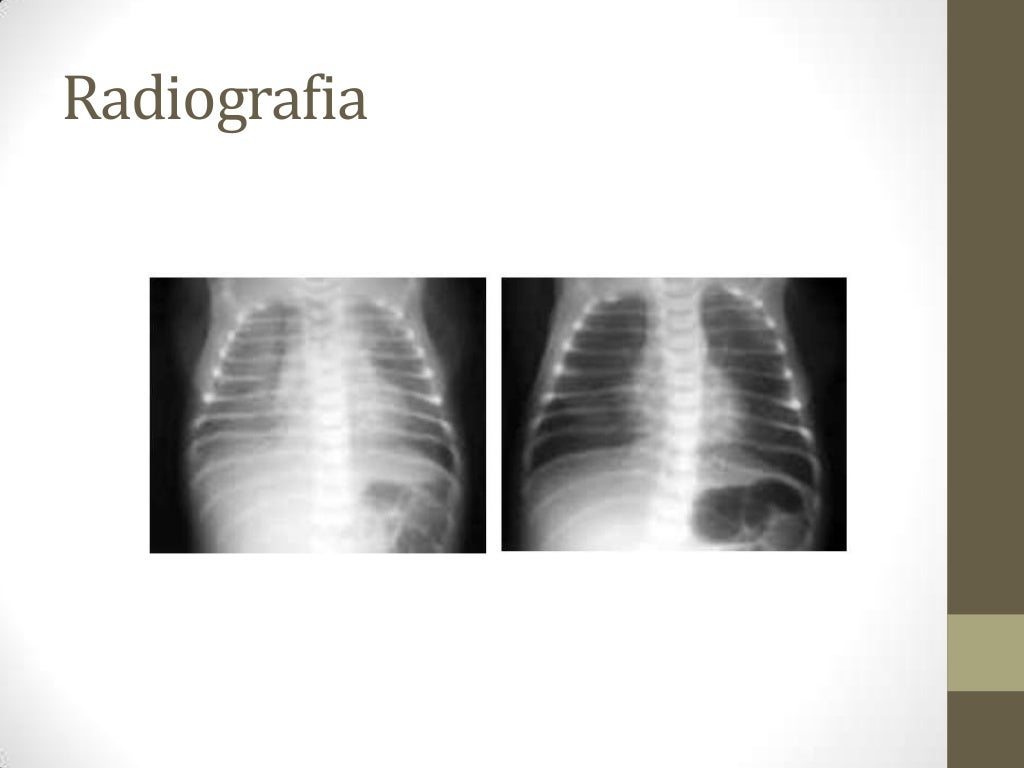

abordou as hipóteses diagnósticas de Síndrome do Desconforto Respiratório do. recém-nascido (SDR), além de pneumonia inicial por estreptococo do grupo B e. sepse. Devido à anamnese, ao quadro clínico e aos achados dos exames de. radiografia e de gasometria, o RN foi diagnosticado com SDR. Lactente foi intubado, submetido à ventilação.